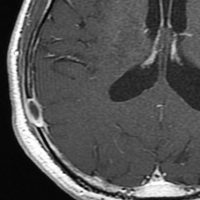

51歳の男性にみられたものです。脳ドックをきっかけにみつかりました。何もないところから発生して増大してまた3ヶ月くらいで消失していきます。左上から1月間隔くらいのMRIです。

もちろん生検手術などしません。

ガドリニウム像です。極期を過ぎているのでリング状増強で,これも縮小消失していきます。